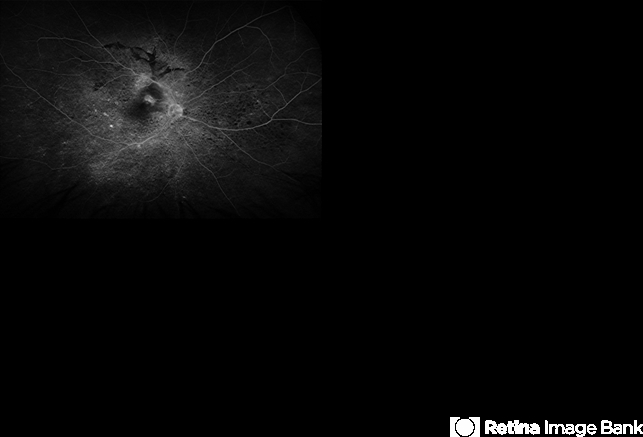

- Vogt-Koyanagi-Harada, pseudotumor, subretinal fibrosis, Fluorescein angiography, granulomatous uveitis, choroiditis

Optos California, fluorescein angiography modality - Description

- Fluorescein angiography image from a 36-year-old woman with chronic Vogt-Koyanagi-Harada (VKH) syndrome showing a pseudotumor-like lesion with late-phase staining and no active leakage. The image highlights subretinal fibrosis in the right eye, stable under long-term immunosuppressive therapy with mycophenolate mofetil and adalimumab. No signs of active choroiditis are present, confirming a quiescent phase.